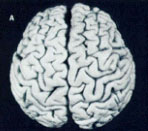

Though she’s received plenty of media attention for her work with men’s and women’s brains, Dr. Witelson is probably known best for her study of Albert Einstein’s brain. She was approached by the person who had Einstein’s brain removed at autopsy. He wanted her to look for anything exceptional. Dr. Witelson: “Of course I said yes!” So, in 1996 Dr. Witelson began her comparison of Einstein’s brain to those in the Brain Bank. She published The exceptional brain of Albert Einstein in 1999. In it, Dr. Witelson and her co-researchers showed that Einstien’s brain was 15% wider in the inferior parietal region of the brain on both the right and left side. The inferior parietal region of the brain is thought to be related to mathematical thinking and visuospatial intelligence. This particular case study suggests that subtle differences in the brain can have major behavioural correlates! |